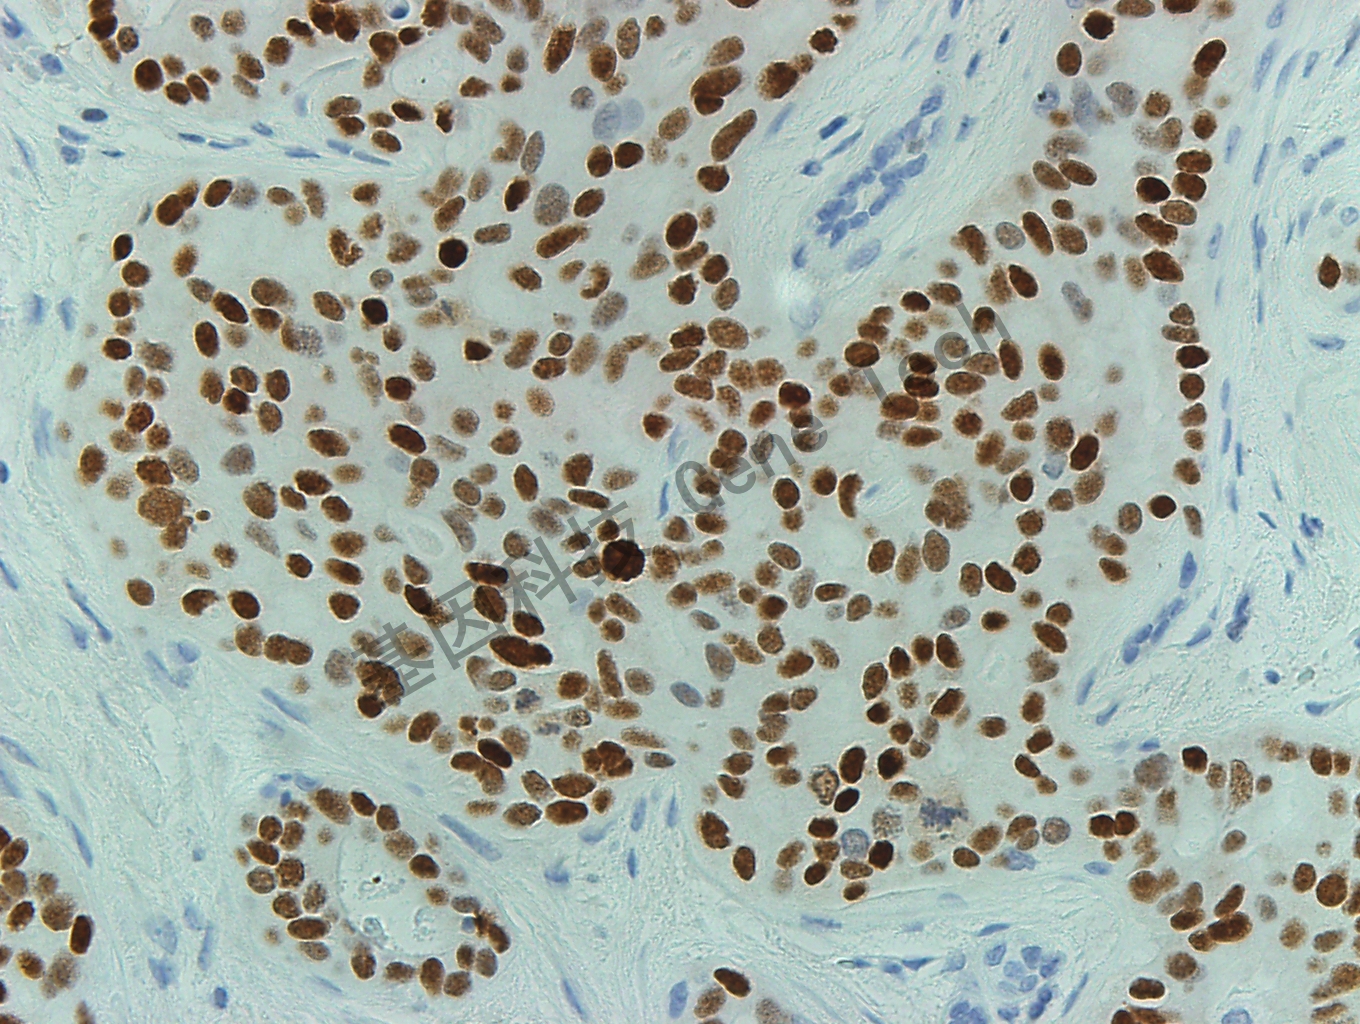

乳腺癌石蜡切片,用 ER(GT2056)染色,细胞核强阳性,DAB 显色。